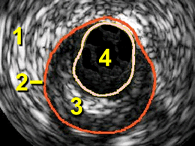

Label the IVUS image below

Adventitia???/?